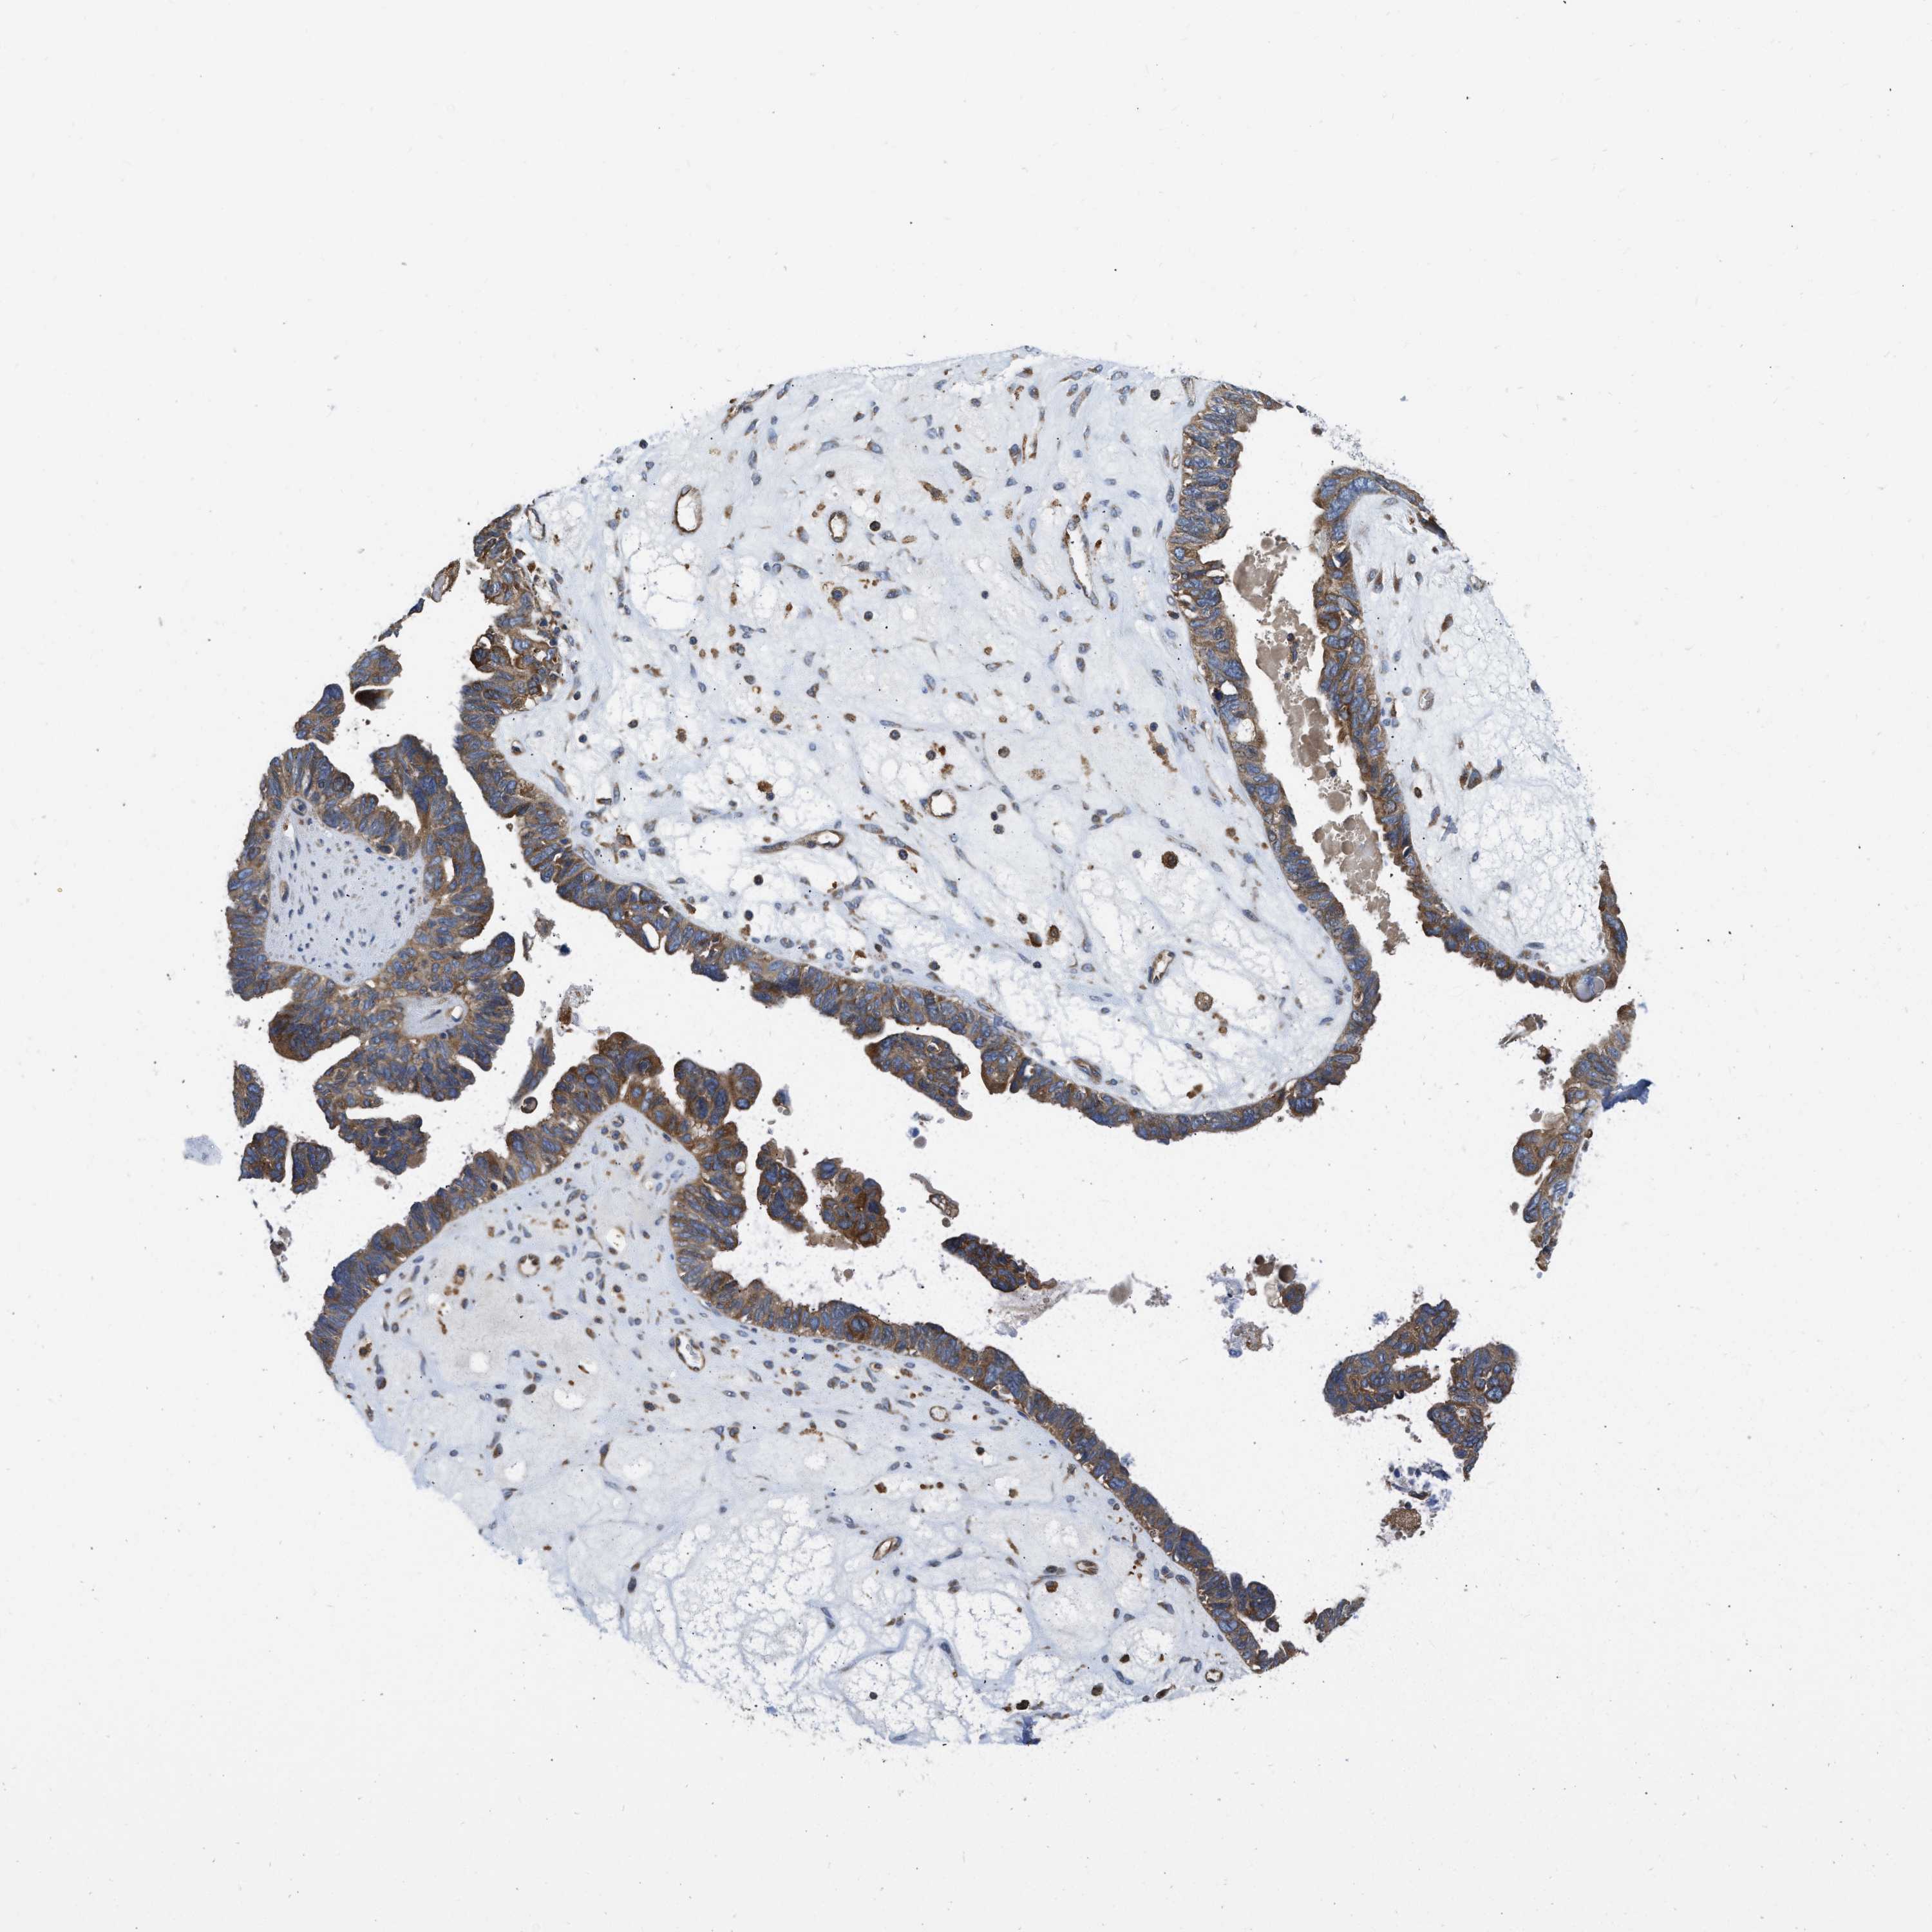

OVARIAN CANCER - Protein expressioni

A mouse-over function shows sample information and annotation data. Click on an image to view it in a full screen mode. Samples can be filtered based on level of antibody staining by selecting one or several of the following categories: high, medium, low and not detected. The assay and annotation is described here.

Note that samples used for immunohistochemistry by the Human Protein Atlas do not correspond to samples in the TCGA dataset.

Antibody stainingi

Antibody staining in the annotated cell types in the current human tissue is reported as not detected, low, medium, or high, based on conventional immunohistochemistry profiling in selected tissues. This score is based on the combination of the staining intensity and fraction of stained cells.

Each image is clickable and will lead to virtual microscopy that enables deeper exploration of all samples and also displays staining intensity scores, fraction scores and subcellular localization as well as patient and tissue information for each sample.

Antibody HPA004747

Antibody HPA004886

Antibody CAB019322

Cystadenocarcinoma, serous, NOS

Carcinoma, endometroid

Carcinoma, NOS

Cystadenocarcinoma, mucinous, NOS